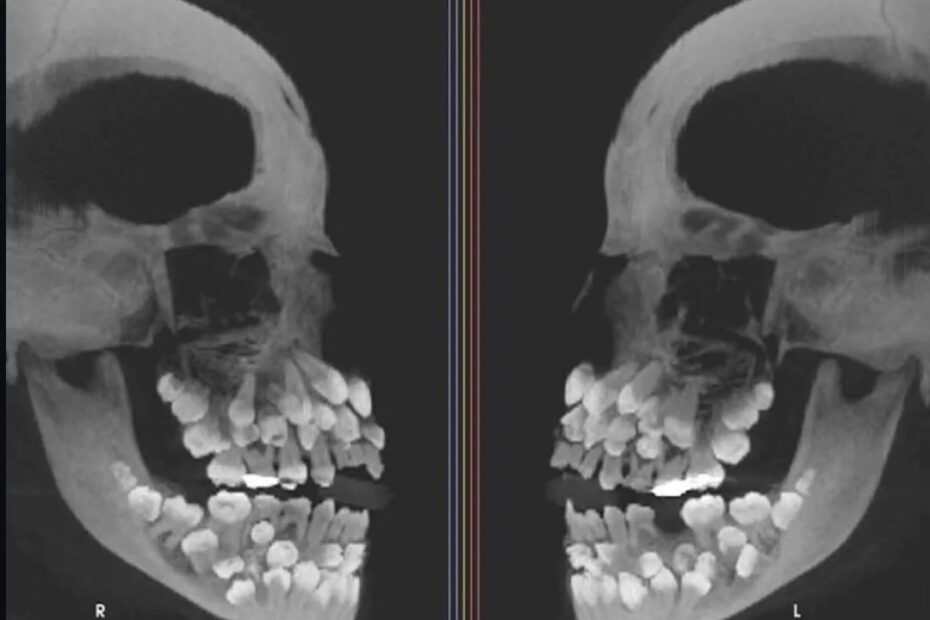

Гипердонтия. Лечение. Гипердонтия (или сверхкомплектные зубы) — это стоматологическая аномалия, при которой у человека формируется и прорезывается больше зубов, чем положено по норме. Если в норме у взрослого… Подробнее »Гипердонтия. Диагностика, причины, лечение